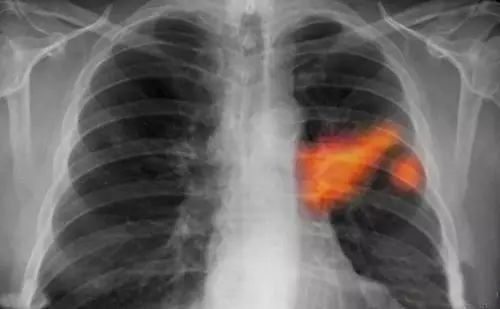

前几天,武昌68岁的王大伯到社区做免费体检,结果发现肺上有一圈阴影。随后在武汉市第三医院系列检查发现,肺癌晚期合并肝脏转移。

详细询问病史,武汉市三医院消化内科医生黄莎莎终于发现蛛丝马迹,这么多年来,爹爹一直爱好烹饪,但炒菜时不习惯开抽油烟机;而且每次做饭都喜欢把油锅烧的滚烫冒烟再开始炒菜。

医生认为,老人长期暴露在厨房重油烟环境中,是患癌的诱因。油烟对身体的致命伤害,已经得到相关证实。此前,上海公布一项长达5年的肺癌流行病学调查发现,女性长期在厨房做饭时接触高温油烟,会使其患肺癌的危险性增加2—3倍。

专家调查后认为,由于厨房做饭时高温油烟产生有毒烟雾,使局部环境恶化,有毒烟雾长期刺激眼和咽喉,损伤呼吸系统细胞组织,如果不加以保护,很容易使肺癌高发。